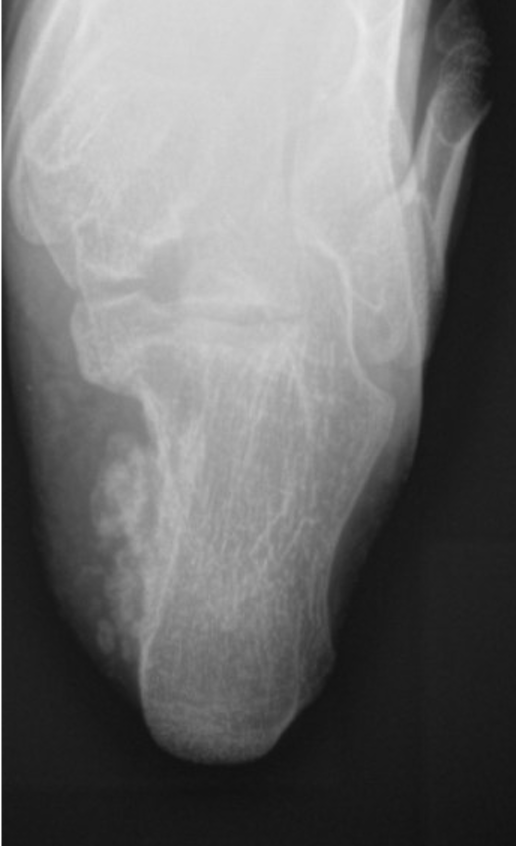

This is a 20-year-old female who presented with a history of a multiply recurrent osteochondroma of her left calcaneus removed in the past by Podiatry. The first excision was when she was 12 years old, and the lesion was thought to be an accessory calcaneus. She was found to have a recurrence at the age of 17, and the lesion was again removed by podiatry. Pathology from this case was consistent with an osteochondroma. It was then, at age 18, that the patient presented to orthopedic oncology for recurrence of the lesion. She presented with a painful bump on her heel that had been slowly increasing in size, similar to her previous presentations to podiatry. Axial radiograph and a select cut of the MRI taken at the time of her initial evaluation by orthopedic oncology are shown in Figs. (1 and 2). Given that the patient was symptomatic, the decision was made to proceed with surgical resection.

Axial radiograph demonstrating bony outgrowth off the posterior aspect of the calcaneus, findings consistent with osteochondroma.